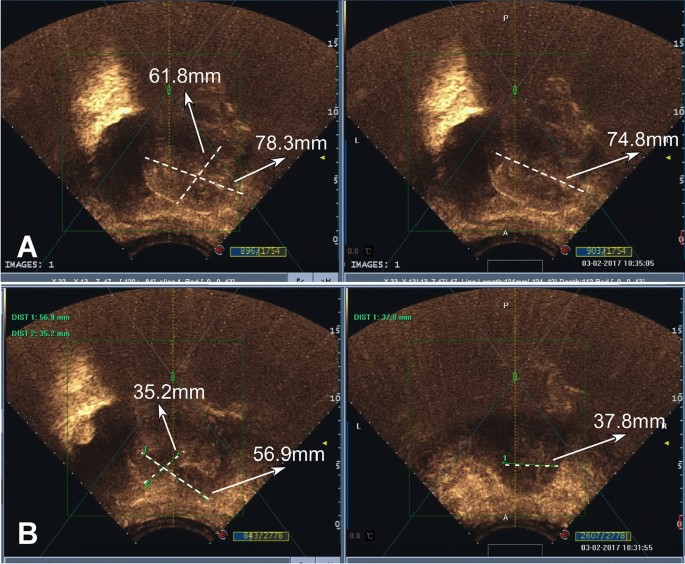

A total of 131 patients with adenomyosis aged 27–53 (mean 39.0 ± 5.2) years were enrolled to undergo the HIFU combined with the LN-IUS treatment (Figs. 2 and 3). The main presentations were increased menstrual volume (> 80 mL, n = 82), menstrual changes (n = 98), anemia (n = 65), dysmenorrhea (n = 78) and infertility (n = 6). The size of the lesion ranged 2.0 cm-10.5 cm (mean 5.3 ± 1.2) with a mean volume of 39.5 ± 3.6 mm3 and a mean time of treatment of 2.6 ± 0.6 (1–4) hours. HIFU treatment was technically successful in all patients (100%) without any difficulty or causing any complications.

A woman in their 30 s had dysmenorrhea and increased menstrual volume and was found to have uterine adenomyosis. (A) Before high-intensity focused ultrasound (HIFU) treatment, the lesion measured 61.8 mm × 78.3 mm × 74.8 mm on ultrasound imaging. (B) After HIFU treatment, the lesion was reduced to 35.2 mm × 56.9 mm × 37.8 mm.